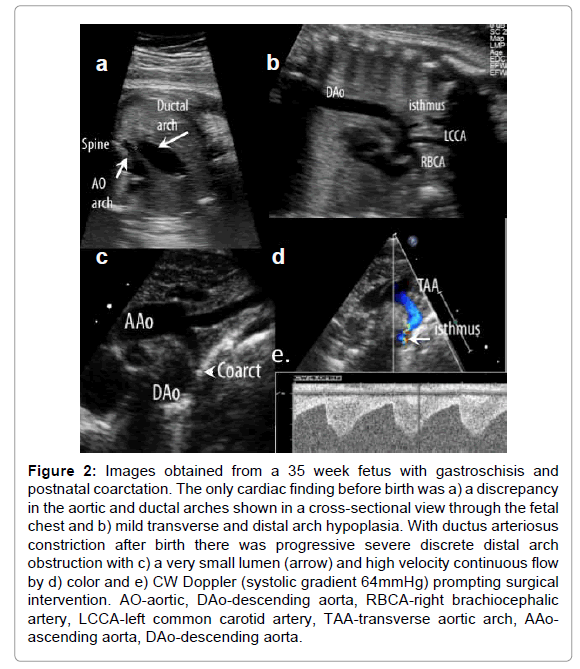

To date, most forms of congenital structural heart disease have been successfully diagnosed in utero, and the details of the cardiovascular anatomy defined including evaluation of systemic and pulmonary venous connections (Figure 1) and aortic and ductal arch position relative to the trachea, are often quite comparable to that of postnatal exams [11-13]. However, the unique parallel circulation of the fetus with right and left ventricles that have comparable filling pressures and afterload, the presence of fetal shunts, and the lack of clinical information beyond noninvasive imaging provides unique challenges to defining lesion severity. For instance, retrograde ductus arteriosus flow in lesions with pulmonary stenosis heralds critical obstruction [14]; however, in its absence, the severity of pulmonary outflow obstruction is often grossly inferred by the size and growth of the main pulmonary artery and its size relative to the aorta [15,16]. Even then, monitoring of systemic oxygen saturations after delivery until ductal closure is still the standard of care. Subtle discrepancies in ventricular, great artery and, most consistently, arch size may be the only abnormalities identified that lead to a suspected diagnosis of discrete juxtaductal coarctation of the aorta which clinically manifests postnatally only after the ductus arteriosus begins to constrict (Figure 2) [17,18]. Occasionally in more severe coarctation, however, distal arch hypoplasia and a posterior shelf may be identified, but even then, determining whether the lesion will warrant neonatal surgical intervention may not be possible until after ductal constriction in the neonatal period [19]. Finally, differences in ventricular preload before and after birth result in an inability to consistently determine whether or not a fetal left or right ventricle that appears borderline in dimension will be sufficient to sustain the systemic or pulmonary circulation after birth. Thus our prenatal counseling must take into consideration such limitations. Our postnatal management, as well, cannot be fully guided by prenatal findings. A small fetal left heart associated with coarctation of the aorta, for instance, may have more potential to dilate with augmented preload over the first several days after birth than what might have been predicted based on prenatal features (unpublished observations). Better delineation of structural and functional features of a borderline ventricle that will not be sufficient to sustain the systemic or pulmonary circulation after birth is critical for improved prenatal counseling and postnatal management. Certainly, this is also an area within which we struggle in the management of patients postnatally.

clinical-experimental-cardiology-postnatal-coarctation

Figure 2: Images obtained from a 35 week fetus with gastroschisis and postnatal coarctation. The only cardiac finding before birth was a) a discrepancy in the aortic and ductal arches shown in a cross-sectional view through the fetal chest and b) mild transverse and distal arch hypoplasia. With ductus arteriosus constriction after birth there was progressive severe discrete distal arch obstruction with c) a very small lumen (arrow) and high velocity continuous flow by d) color and e) CW Doppler (systolic gradient 64mmHg) prompting surgical intervention. AO-aortic, DAo-descending aorta, RBCA-right brachiocephalic artery, LCCA-left common carotid artery, TAA-transverse aortic arch, AAoascending aorta, DAo-descending aorta.